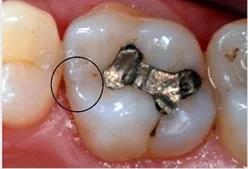

去腐备洞

去腐备洞:打开窝洞可以清晰的看到邻面龋坏的程度,和龋齿探测仪中所检查的龋坏窝洞范围及形态基本一致。